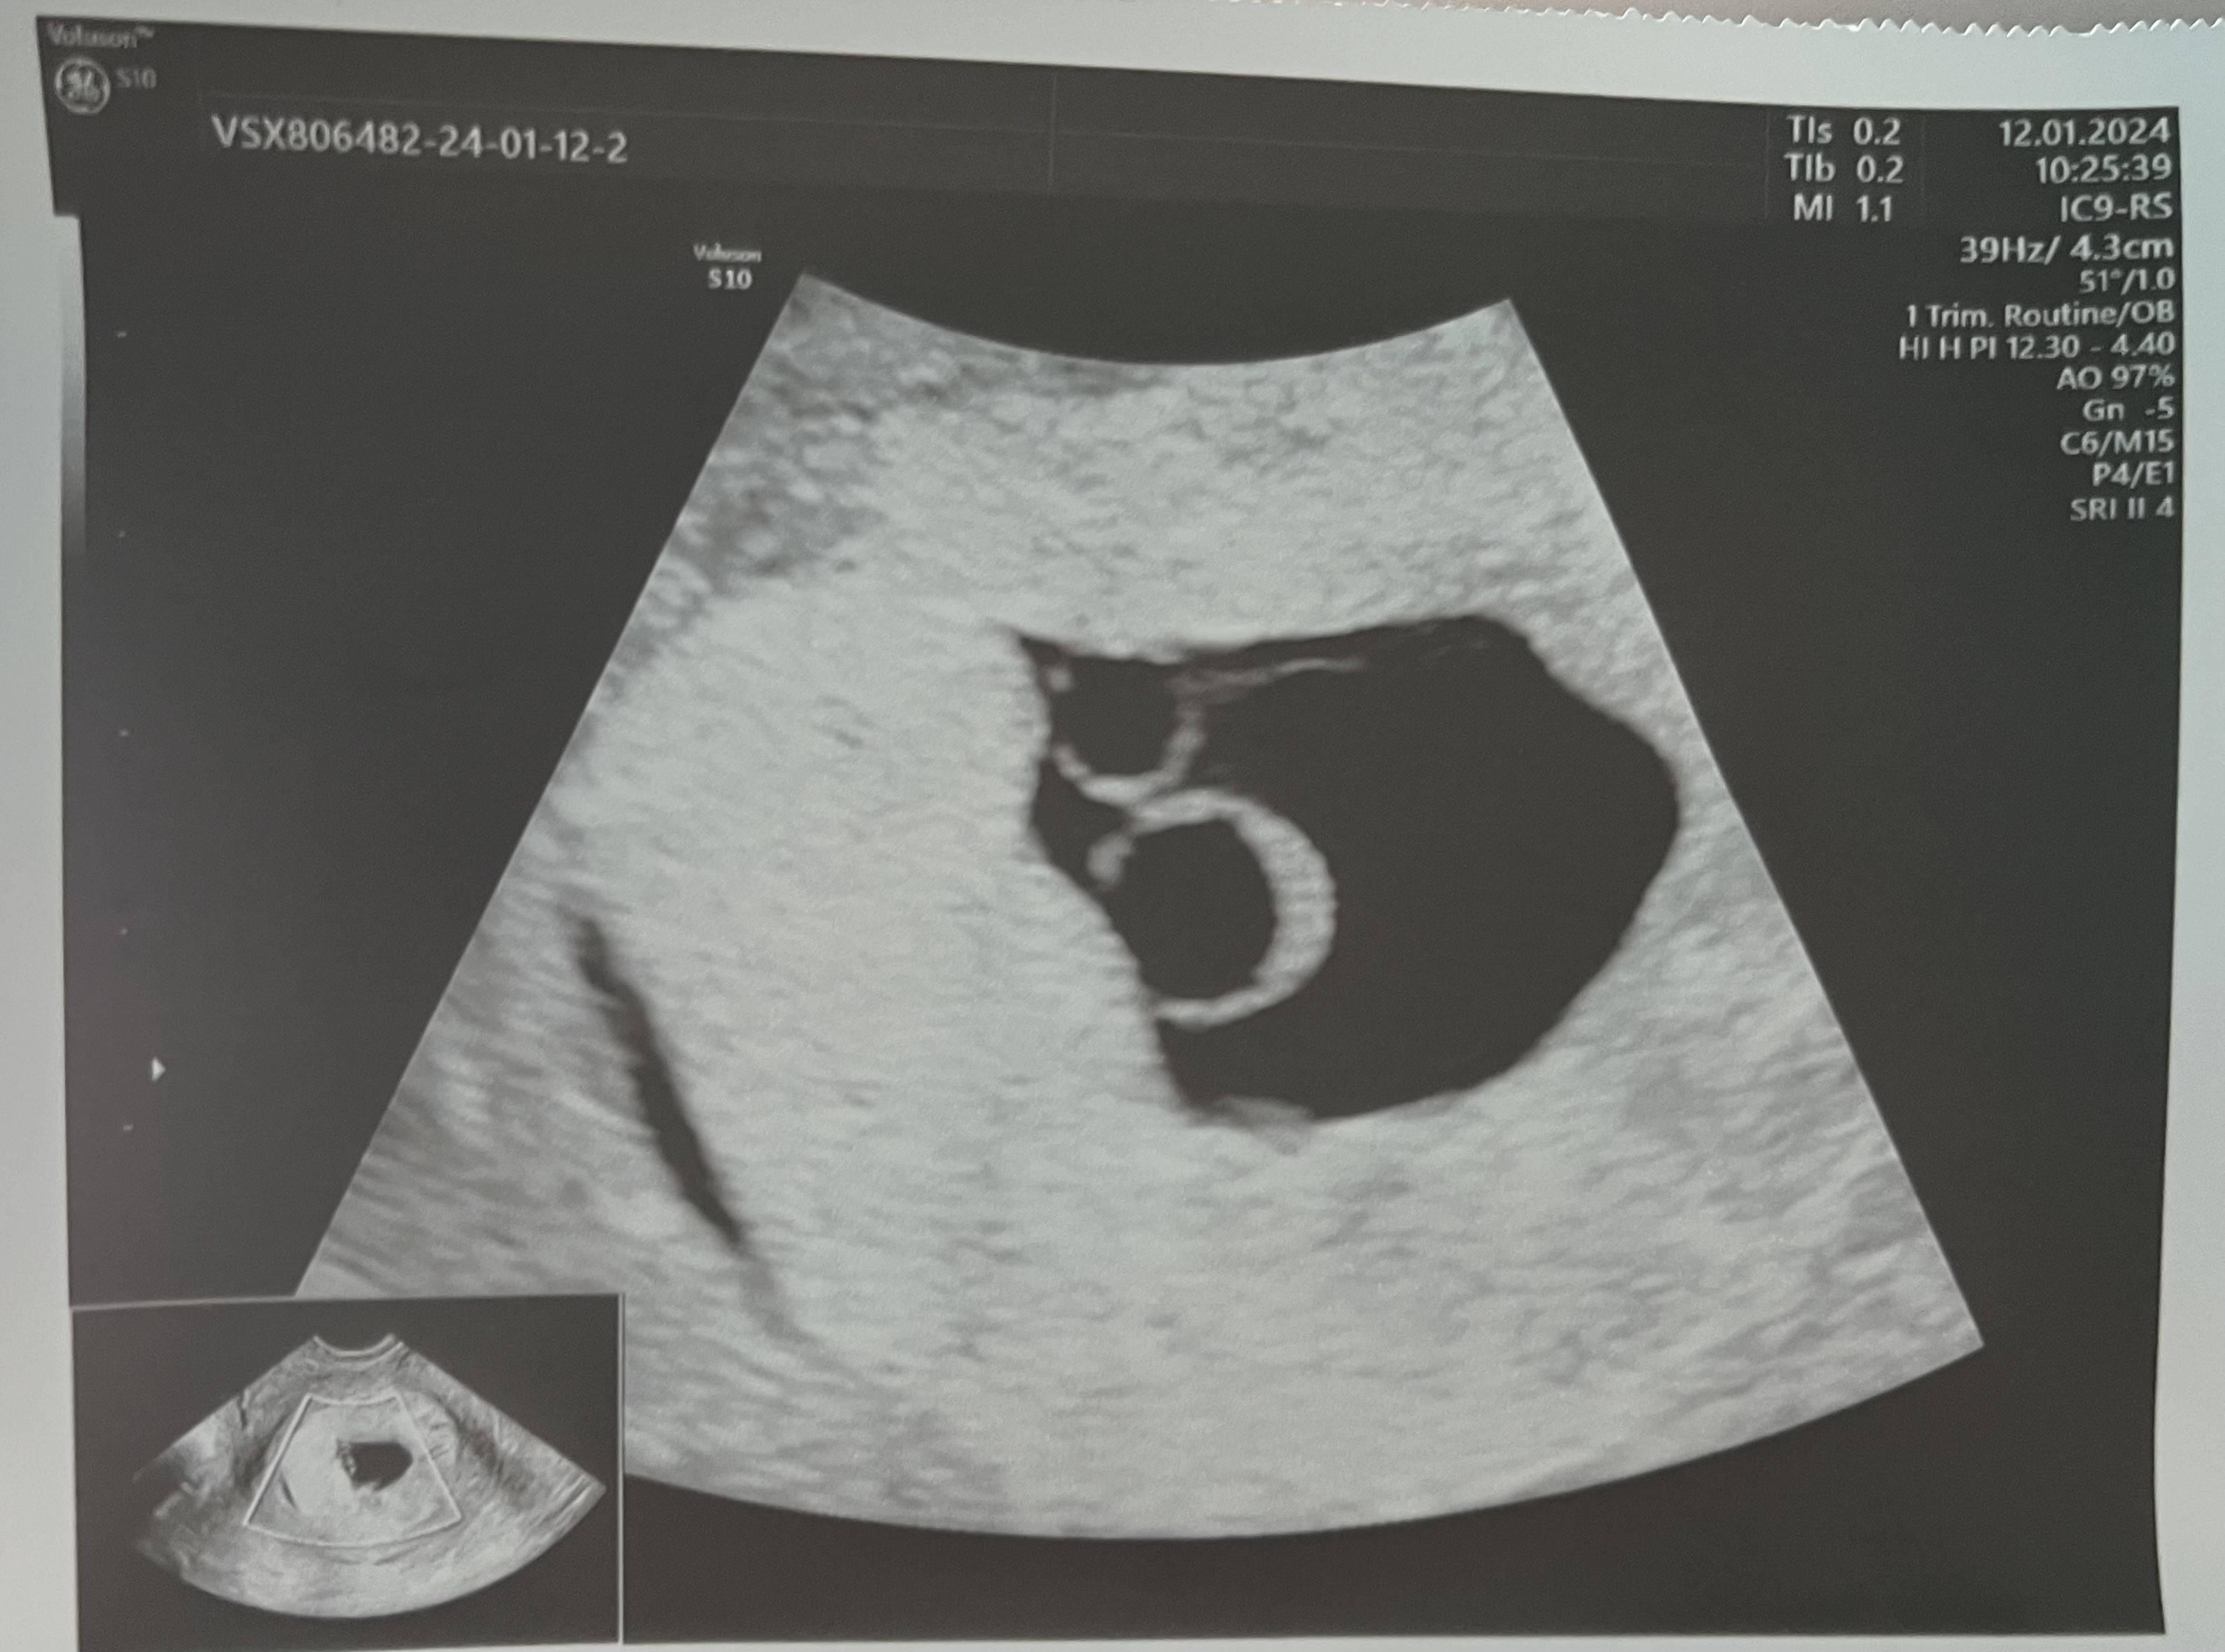

A jednak zwrot akcji… Pojawił się zarodek, jeszcze bez serduszka, wielkości odpowiadającej 6 tygodniowi ciąży. Ale… pojawił się też drugi pęcherzyk ciążowy, choć jeszcze bez zarodka. Badało mnie dwoje lekarzy i wygląda na to, że jestem w ciąży bliźniaczej jednojajowej 🫣 Kolejna wizyta 22.01.

Zobacz załącznik 1602307